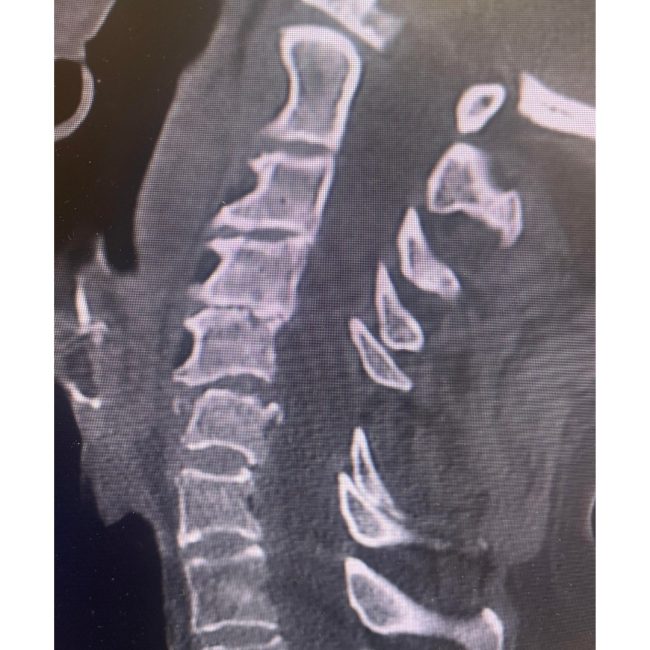

89-Year-Old with C5–6 Fracture-Dislocation: Surgical Stabilization

“Taking a call at a Level 1 trauma center is stressful and takes time away from family and a neurosurgeon’s precious free time. I was reminded recently why I still feel passionate about taking a Level 1 trauma call when I met this simply miraculous 89-year-old woman. She was involved in a motor vehicle collision…